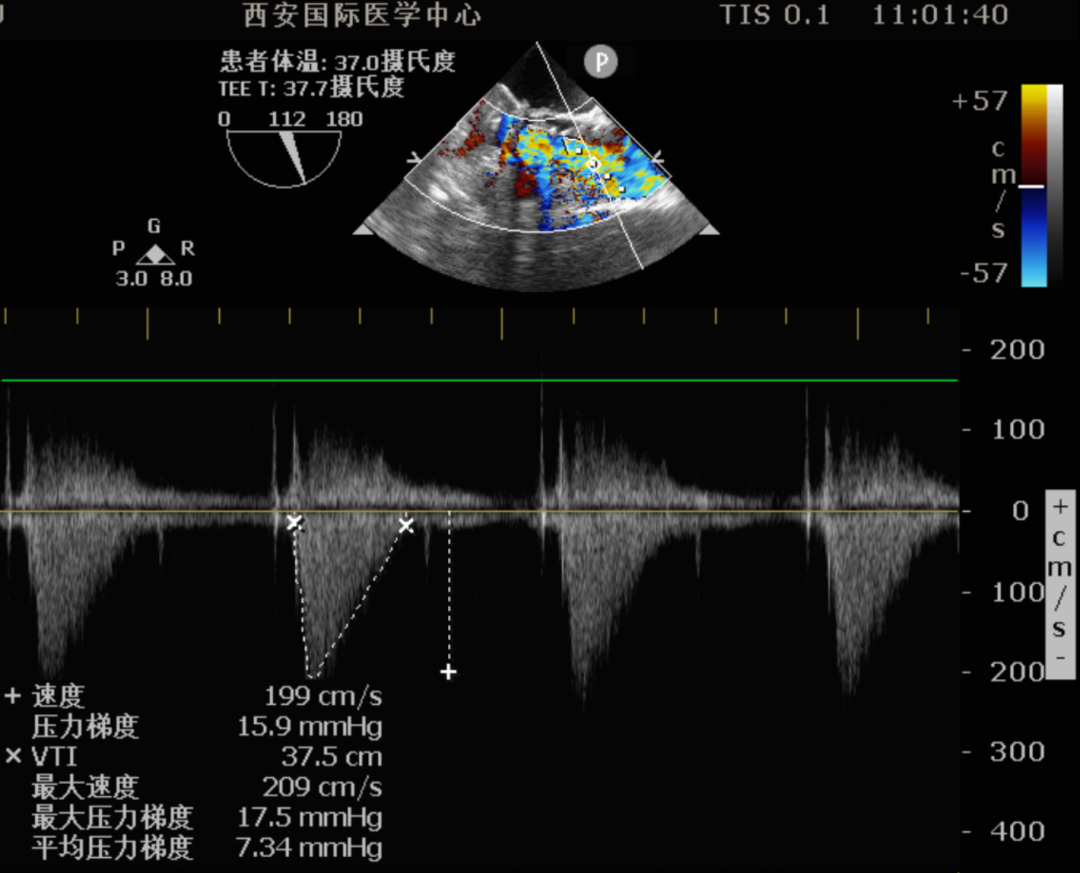

• 心脏超声:主动脉瓣重度狭窄(峰值压差 70mmHg,平均压差约 43mmHg),二尖瓣置换术后,左房增大,肺动脉高压(轻度),左室舒张功能减低,收缩功能正常,三尖瓣中量返流

Step 6.超声观察:人工瓣膜位置、压差、密封良好,二尖瓣开合正常。

11.png

平均压差由术前43mmHg降至7mmHg,术前导管压差45mmHg,术后导管压差3mmHg;左心室收缩功能稳定,跨瓣压差显著改善,患者循环状态平稳。